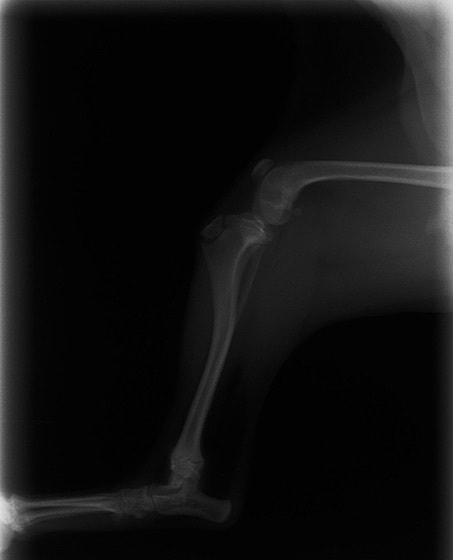

症例3:キルシュナーワイヤーのピンニングによる整復

ペルシャ猫 11ヶ月齢 雄

他院にて左大腿骨遠位の成長板骨折(salter-harrisⅠ型)が認められており、治療相談を目的として来院。当院にて、キルシュナーワイヤーを用いたピンニングにより骨折部位の整復を行いました。術後の経過は良好で、現在も経過観察中です。

術前レントゲン

術後レントゲン